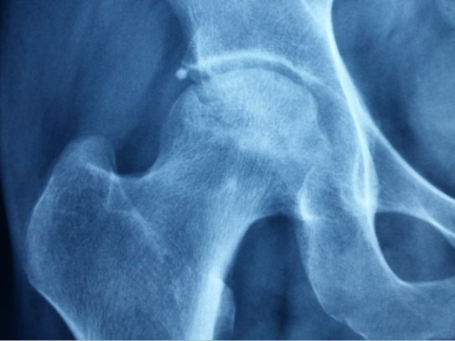

郑州股骨头坏死专科医院:股骨头坏死三期怎么治疗

郑州股骨头坏死专科医院介绍已经到了第三期,说明股骨头的完整性、基本性还是比较好的,只…[详情]